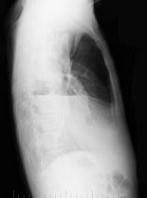

问题 男性患者,64岁,咳嗽高热多日,无痰中带血,X线检查如图所示,最合理的诊断是 ( )

选项 A、右肺不张 B、右支气管扩张 C、右侧胸腔积液并肺脓肿 D、右肺炎 E、右侧胸腔积液

答案 C